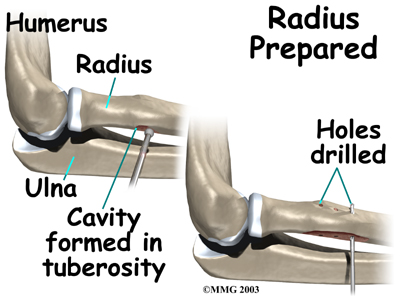

The original attachment on the radius, the radial tuberosity, is . An instrument called a burr shaves off the surface of the tuberosity. The burr is then used to create a small cavity in the bone for the tendon to fit inside. Three small holes are drilled into the top of the rim of bone to secure the sutures.

The tendon is passed between the radius and ulna, exiting through the second incision that was made on the back of the forearm. The sutures are threaded into the three holes that were drilled into the rim of the radial tuberosity. The surgeon ties the sutures, securing the . When the surgeon is satisfied with the repair, the skin incisions are closed, and the elbow is placed either in a cast or a range-of-motion brace.